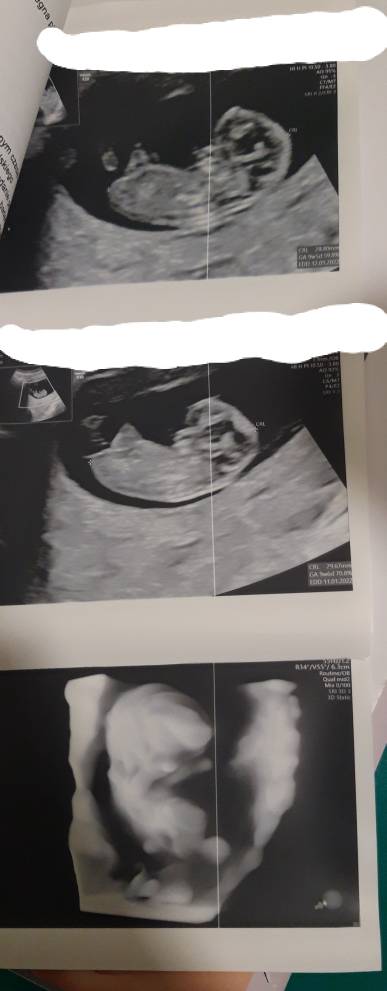

Dziewczyny, czy te wyniki są dobre?

IMG_20210614_183926.jpg